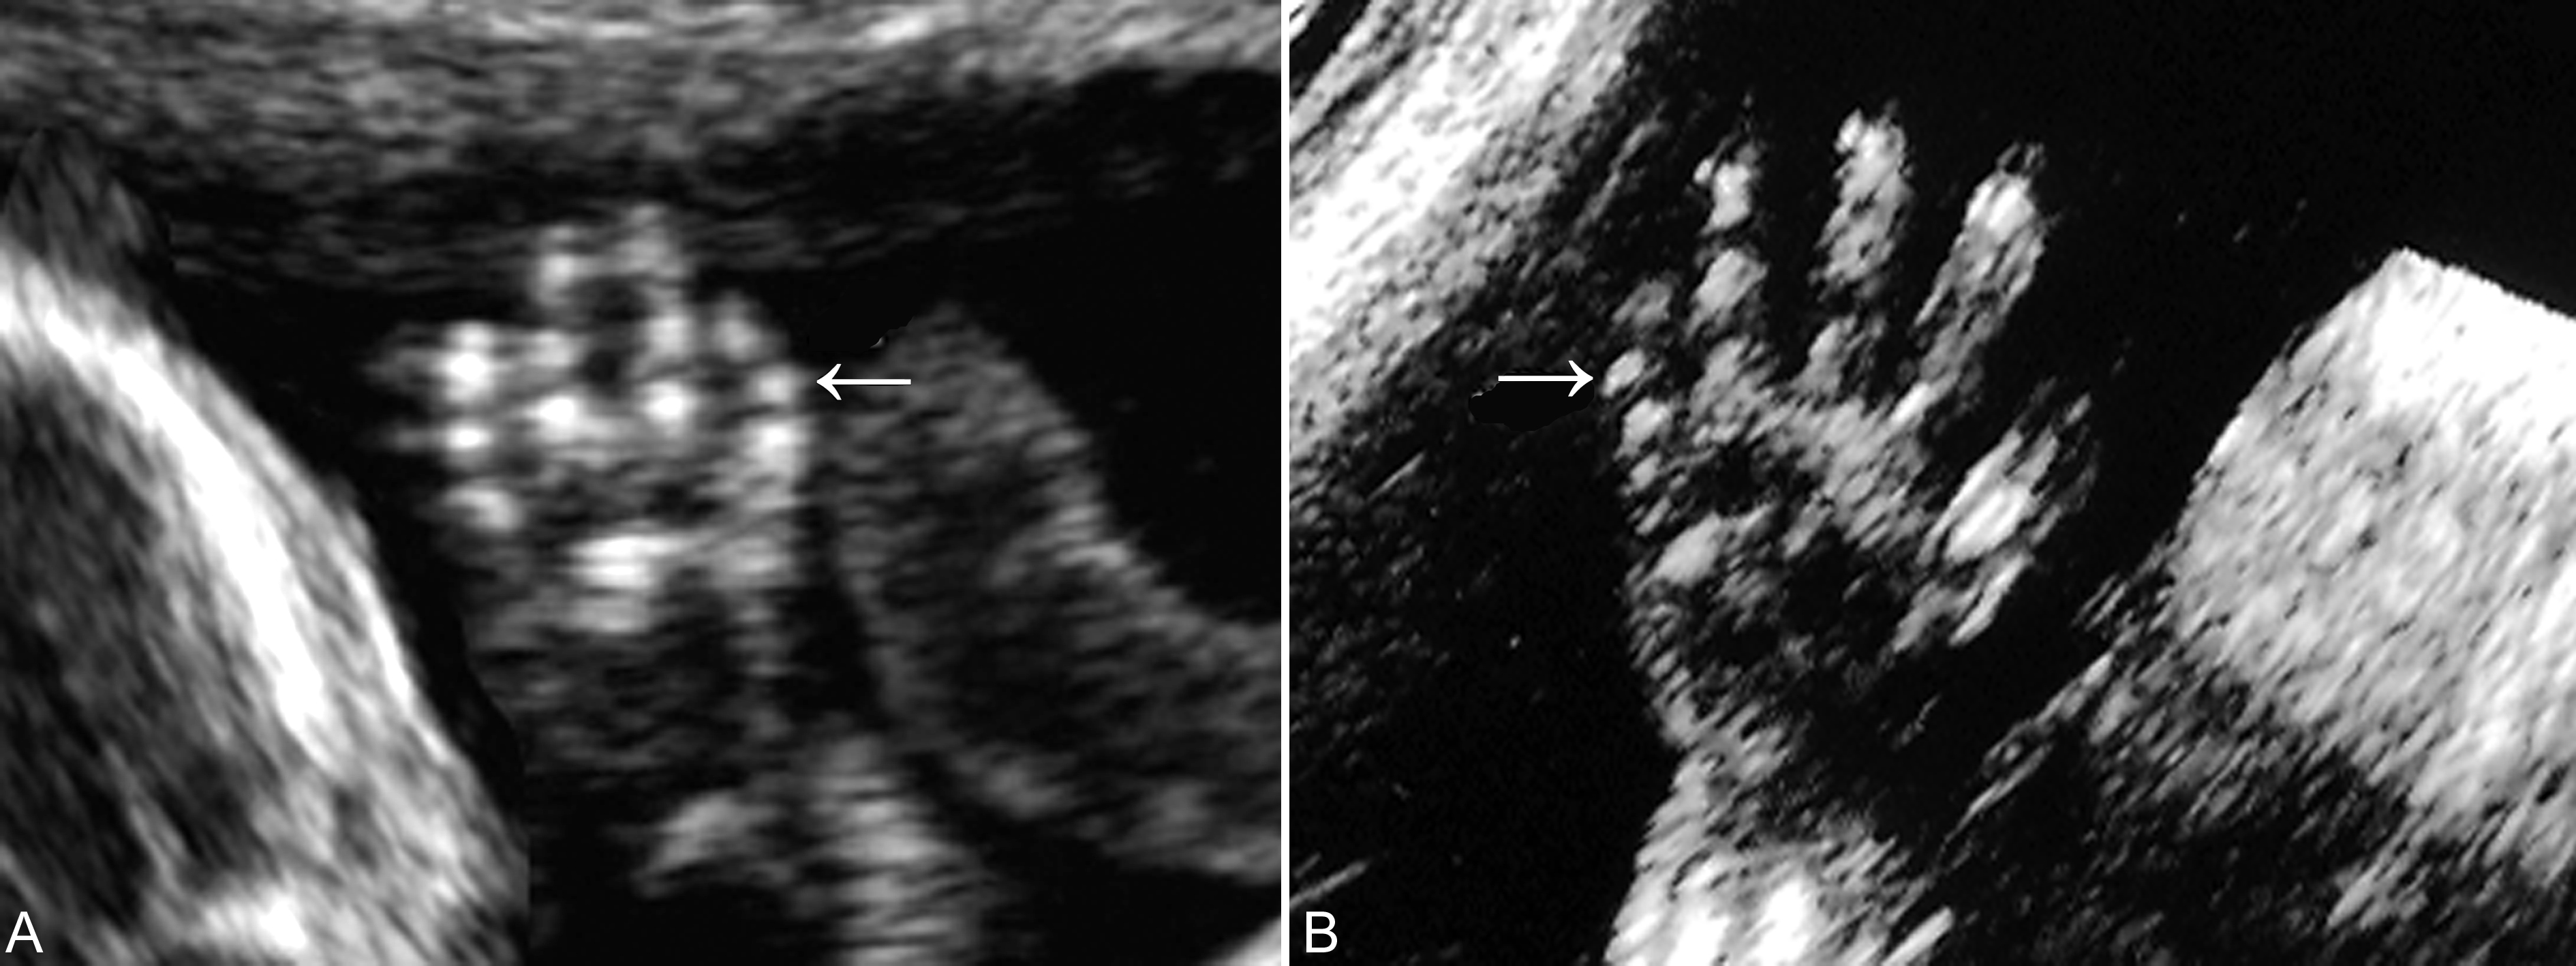

手(足)指(趾)的侧方的重复畸形,包括轴前型和轴后型多指(趾)畸形时,手(足)指(趾)的正常形态多可显示,仅仅是在手的一侧显示额外的回声,多数结构异常或骨骼短小,与正常的手指排列关系明显不一致,较短,指(趾)骨缩短或有弯曲,与相邻指(趾)骨或掌(跖)骨成角畸形(图3,图4)。如果不能显示手(足)指(趾)的正常形态并且指(趾)数增多,则为中央型多指(趾)畸形。显示中央型多指(趾)畸形时需要注意观察多指(趾)与邻指(趾)的关系,如果表面皮肤及皮下软组织完整,则为多指(趾)并指(趾)畸形。产前超声检查发现多指畸形后要注意胎儿头部、胸部、心脏及腹部的检查(图5),发现有无合并的畸形对预后的评估非常重要。

图4轴前型多指畸形声像图(箭头)